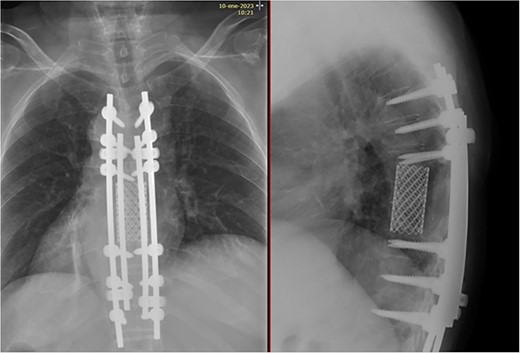

Two years after surgery, adequate clinical recovery continues, with a high-degree satisfaction, persisting mild lumbar pain, and a slight weakness in the right foot. Pertinent X-rays show normal position of the implants with no implant loosening (Fig. 10).

X-rays showing normal position of the implants with no signs of loosening.